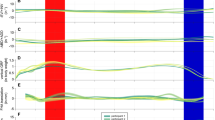

A comparison of the mean positional coordinates of the peroneal tendons before and after the detaching operation of the CFL is shown in Table 1 and Supplementary Tables S2 and S3. Only for the y-axis, the positions of the PLT and PBT were significantly higher with the intact CFL than with the detached CFL (22.9 ± 4.6 mm vs. 21.4 ± 4.3 mm for the PLT; 21.1 ± 5.6 mm vs. 19.6 ± 5.4 mm for the PBT; for each, P < 0.001). These results demonstrated a statistical power value greater than 99% by a post-hoc power analysis. Furthermore, in all 18 samples, Δy had positive values, ranging from 0.2 mm to 2.8 mm for the PLT and 0.1 mm to 3.3 mm for the PBT. The average Δy was 1.5 mm for both tendons, and the 95% confidence intervals for the PLT and PBT were 1.1–1.9 and 1.0–1.9 mm, respectively (Table 1). In contrast, Δx and Δz varied with an inconstant directionality from positive to negative values in both tendons (Table 1 and Supplementary Fig. S1). For the PLT, the extent of Δx and Δz was − 2.6 mm to 1.8 mm and − 1.5 mm to 1.6 mm, respectively. The mean value ± standard deviation (SD) (range) of the LA, indicating the actual moving distance of the tendons, reached 2.0 ± 0.8 mm (0.8–3.5 mm) for the PLT and 1.9 ± 0.9 mm (0.5–3.8 mm) for the PBT.

To confirm the synchronous movement of the PLT and PBT, we prepared scatter plot diagrams of Δy and the LA of both tendons and calculated the correlation coefficients for each parameter (Fig. 4). The diagrams showed a peak distribution roughly in the center and a strong positive correlation for Δy (r = 0.80, P < 0.001) and LA (r = 0.83, P < 0.001).

The scatter plot and histogram of (a) Δy and (b) lift amount (LA) between the PLT and PBT (the plots were created using JMP Pro [SAS Institute Inc., Cary, NC, USA]). Approximately straight lines are shown as the eye guide. The LA was calculated by using the following formula: LA = \(\sqrt {{\Delta }x^{2} + {\Delta }y^{2} + {\Delta }z^{2} }\). PLT peroneus longus tendon, PBT peroneus brevis tendon.